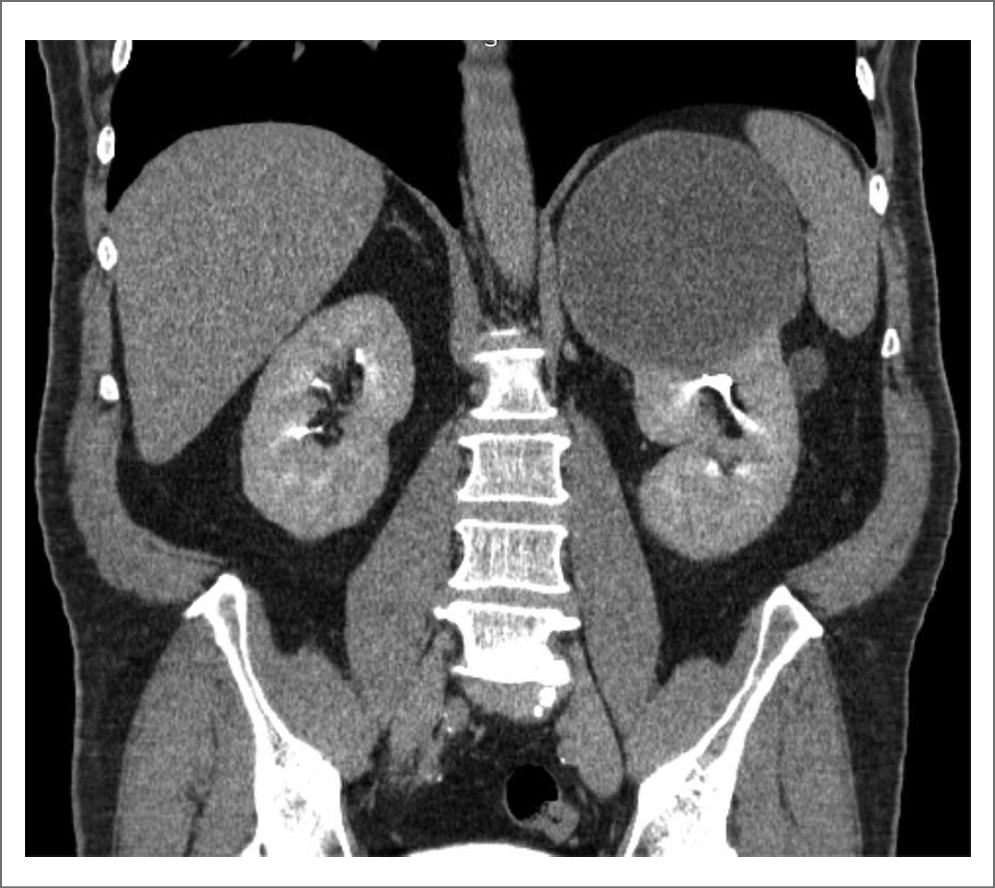

Стоит отметить клинический случай пациента из нашего исследования с кистой почки категории IIF диаметром до 131 мм в верхнем сегменте с тонкой капсулой и наличием пристеночного мягкотканного компонента, не накапливающего контраст. На рис. 1–4 представлены снимки мультиспиральной КТ пациента до операции с внутривенным контрастированием в различных срезах с демонстрационными измерениями. Выполнено оперативное вмешательство – лапароскопическое иссечение стенки кисты. В ходе операции после вскрытия стенки образования эвакуировано до 650 мл коричневой жидкости с желто-коричневыми хлопьями. При получении гистологического заключения верифицирован почечно-клеточный рак, проведена радикальная нефрэктомия в отсроченном порядке. Морфологическое исследование удаленной почки после повторного оперативного вмешательства подтвердило диагноз папиллярной карциномы, тип 2, G2 по Fuhrman. Т3N0M-R0.

Рис. 4. Киста левой почки. Коронарный срез. Экскреторная фаза.